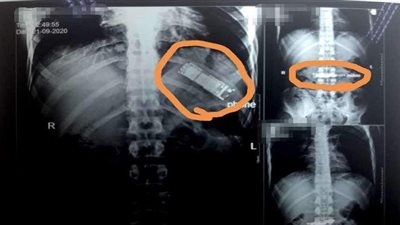

أجرت مستشفى بنها الجامعي بالأمس جراحة خطيرة لمريض ابتلع هاتف محمول

اعلنت مستشفي بنها الجامعي عن تفاصيل انقاذ حياة مريض ابتلع هاتف محمول

أوضحت أشعة تليفزيونية تم إجراؤها بمستشفيات بنها الجامعية عن وجود تليفون محمول بمعدة شخص منذ فترة وصلت لـ 7 أشهر